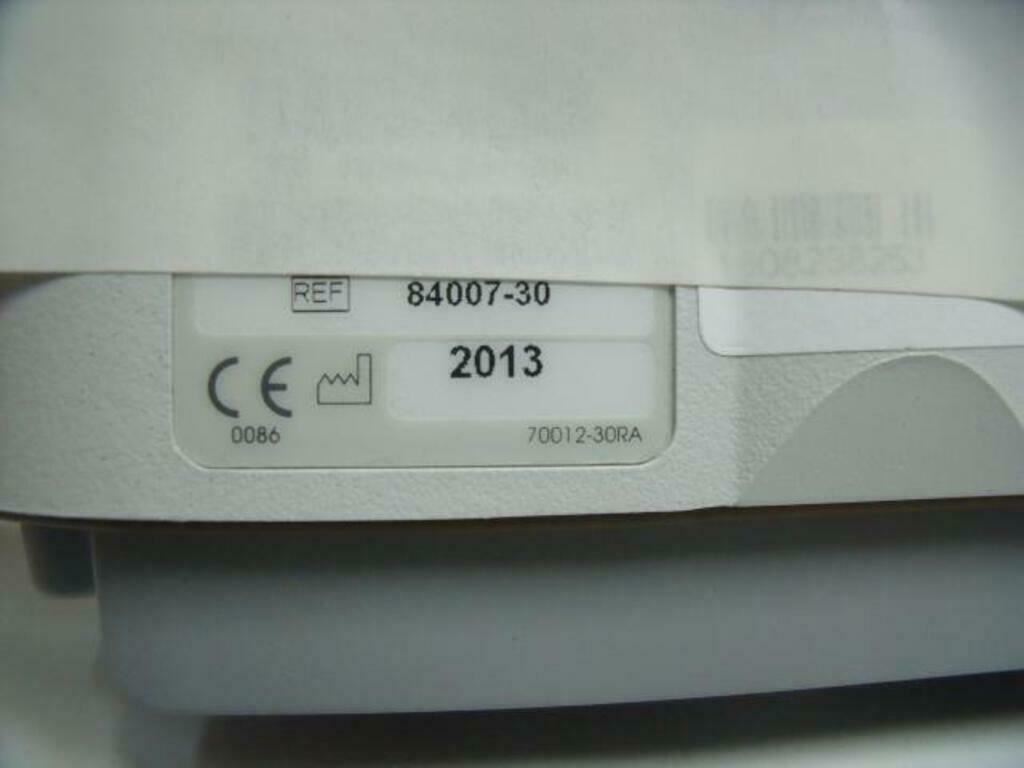

ZONARE 84007-30 L8-3 ULTRASOUND PROBE

In good condition, "as pictured."